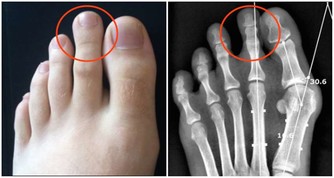

高血壓,是指以體循環動脈血壓(收縮壓和/或舒張壓)增高為主要特徵(收縮壓≥140毫米汞柱,舒張壓≥90毫米汞柱),可伴有心、腦、腎等器官的功能或器質性損害的臨床綜合徵。高血壓是最常見的慢性病,也是心腦血管病最主要的危險因素。

高血壓產生的原因有遺傳因素、精神和環境因素,生活習慣因素等,但是最常見的一個種原因是年齡原因。隨著年齡的不斷增長,40歲以上的中老年群體極易患高血壓,主要原因是人體血管內的各種代謝雜物擁堵與血管中,造成血液流量不穩,出現高血壓現象。作為一種常見的慢性疾病,高血壓可誘發冠心病、中風等多種致命的心腦血管疾病疾病,也被認為是中老年健康的“頭號殺手”,並且患上高血壓很難治愈,像不定時炸彈一樣伴隨終身。